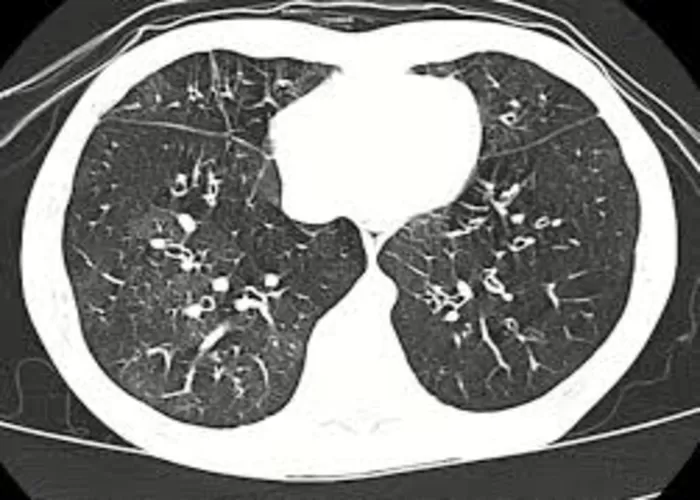

Ilustrasi untuk gejala popcorn lung